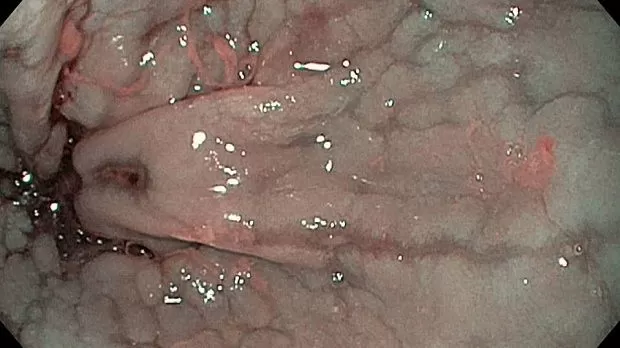

Публикации из социальных сетей: “Cobblestone esophagitis” (эзофагит со слизистой булыжной мостовой)

Авторы: Ondre Kovcov 2019г.

“Cobblestone esophagitis” (эзофагит со слизистой булыжной мостовой) - редкая эндоскопическая находка и ассоциируется с эозинофильным эзофагитом, кандидозом и пищеводом Барретта у взрослых. Он также может быть найден при тяжелом рефлюкс-эзофагите, вторичен к дистальной обструкции гастроинтестинального тракта. В нашем случае - это пациент после с 9-летним стажем бандажирования кардиального отдела желудка, признаками дуоденостаза, фундальной эрозивной гастропатией, расширением пищевода и уровнем жидкости в нем при горизонтальном положении, грыжи ПОД, эрозивно-язвенном дистальном эзофагите.. Пациент просто пришел удалить полип в прямой кишке и заодно посмотреть, что творится в желудке.... Ацетообеление+NBI+биопсия. ИПП на 3-4 мес и повтор для решения о Барретте.